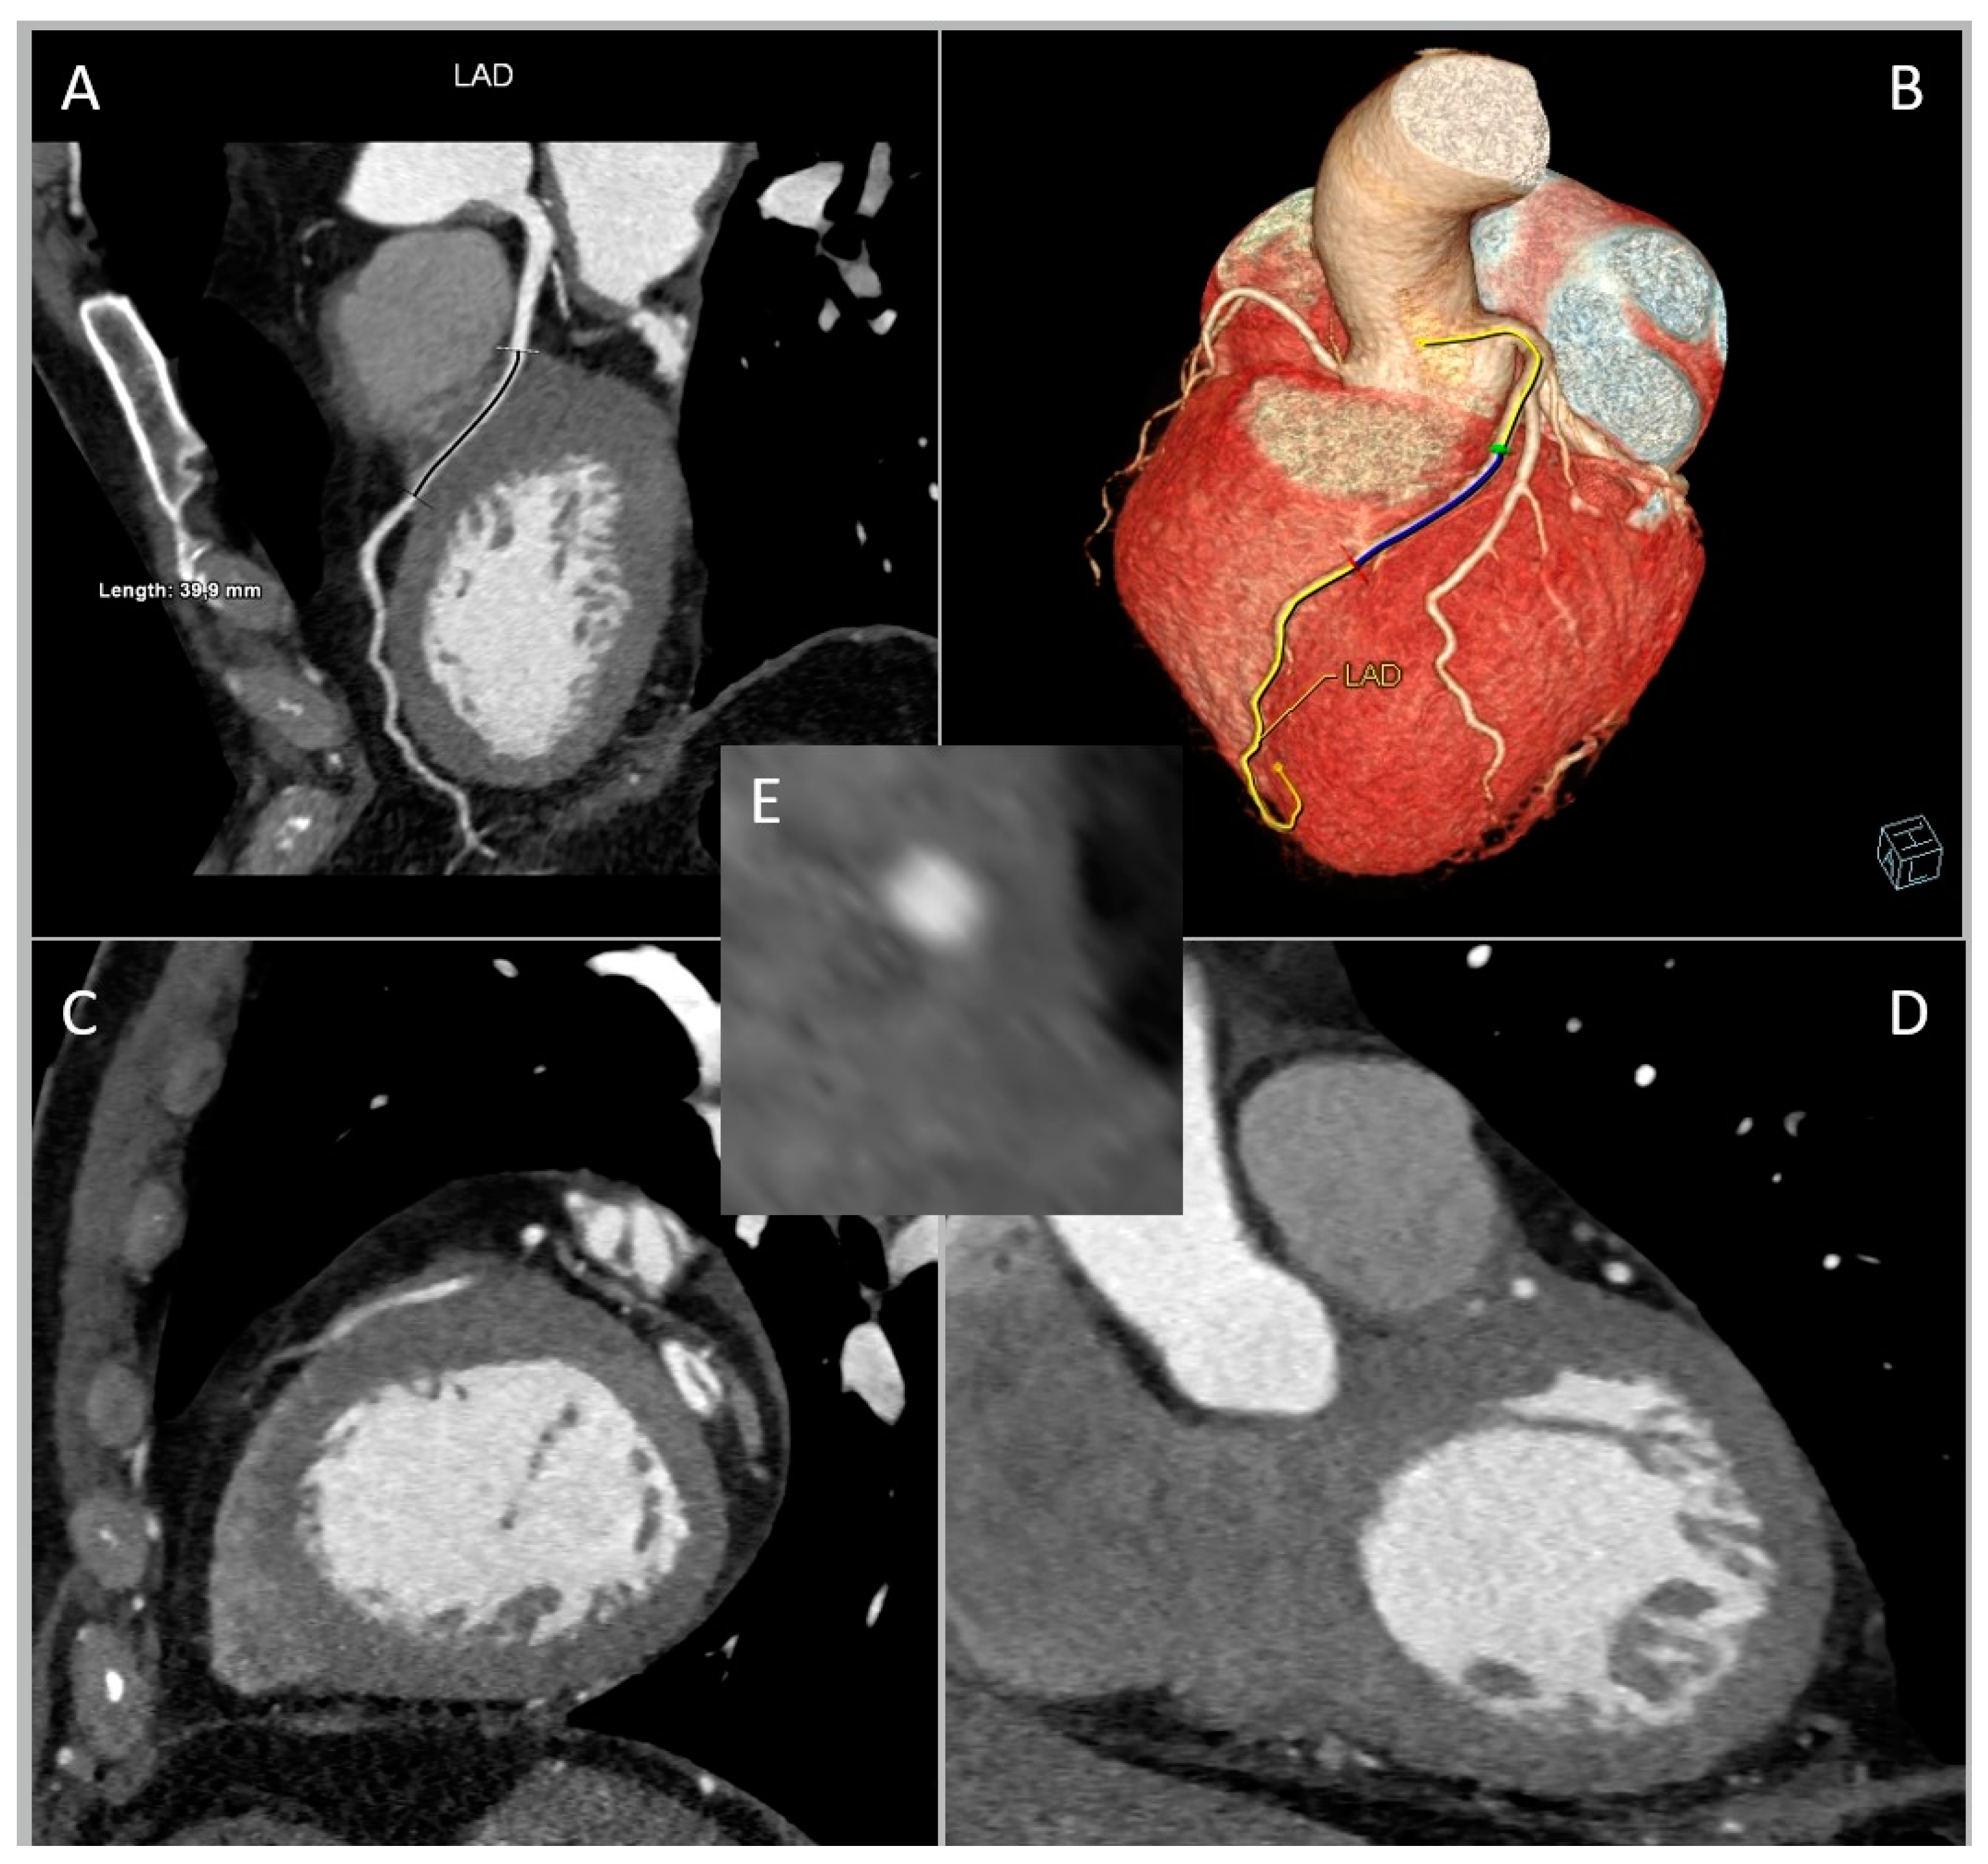

2. CCTA Imaging Protocol

3. Role of CCTA: Anatomical Evaluation